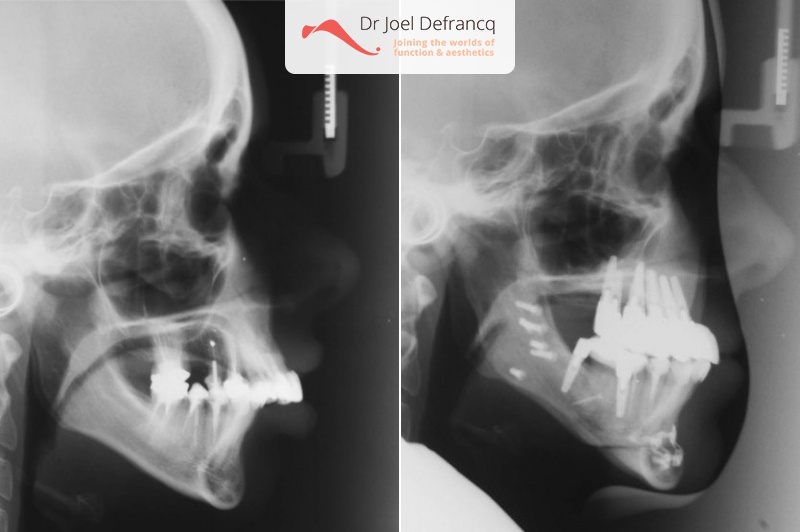

Kaakchirurgie

- Verlenging onderkaak (BSSO)

- Kinchirurgie

- Implantaten met osteotomie